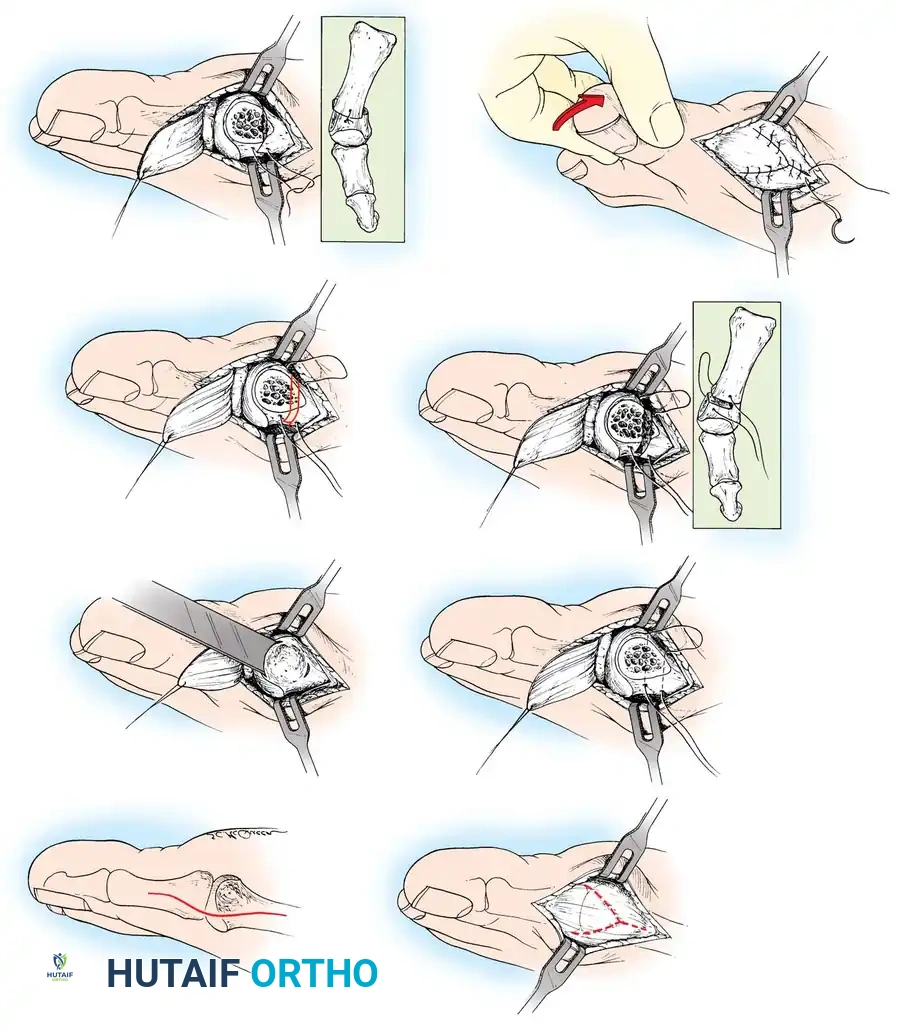

🔪 Surgical Technique 78-2

• If pedal pulses are good, use an Esmarch wrap tourniquet.

• Use 1% lidocaine (Xylocaine) and 0.5% bupivacaine (Marcaine) in equal portions within standard dose limits for the forefoot block.

• Make a straight midline medial incision 1 cm proximal to the interphalangeal joint of the hallux, and extend it proximally to the junction of the distal and middle thirds of the fi rst metatarsal. This lengthy incision is made to avoid excessive traction tension on the skin.

• By blunt dissection, locate the most medial branch of the superfi cial peroneal nerve at the proximal-dorsal edge of the medial eminence, and retract it for protection.

• Carry the dissection to the fi rst metatarsal in the midline medially, beginning in the proximal limit of the wound and extending distally across the midline of the medial eminence and along the proximal phalanx to the distal extent of the wound.

• Raise the deep fl ap of tissue by sharp dissection dorsally, beginning at the junction of the medial eminence and shaft of the fi rst metatarsal.

• Raise the periosteum and capsule dorsally up to one third to one half the width of the metatarsal.

• At the joint, continue the capsular elevation along the extensor hallucis brevis insertion until the proximal third of the proximal phalanx is exposed as far laterally as possible under direct vision. To make exposure easier, have an assistant pronate the hallux as the dissection proceeds laterally. Subperiosteal dissection should expose only the portion of the proximal phalanx that is to be removed.

• Plantarly dissect just enough to expose the plantar aspect of the medial eminence proximally, the tibial sesamoid in the center of the wound, and the plantar-medial corner of the proximal phalanx.

• Supinate the proximal phalanx to expose the plantar corner and proximal third of the shaft for the sharp dissection. The proximal phalanx is round on three sides, but its plantar surface is fl at and even concave in the midline where the fl exor hallucis longus tendon passes. This change in contour must be taken into account when dissecting to avoid injury of the fl exor hallucis longus tendon.

• By blunt dissection, identify the fl exor hallucis longus tendon, and retract it plantarward with a small right-angle retractor to protect it throughout the dissection of the proximal phalanx.

• Resect the medial eminence at the sagittal groove, beginning dorsally at its distal edge and directing a 9-mm oscillating blade

🔪 Surgical Technique 78-2

(or osteotome) plantarward and slightly medially (5 to 10 degrees).

• Remove the base of the proximal phalanx at the metaphysealdiaphyseal junction, which usually constitutes the proximal third of the phalanx (Fig. 78-30A and B). To prevent damage to the fl exor hallucis longus and the neurovascular bundles, place a retractor over the bone dorsally and plantarward, and rotate the phalanx into view. Also, do not allow the saw blade to exit bone more than 1 to 2 mm.

• When the osteotomy has been completed, grasp the basilar fragment with a small Kocher clamp or towel clip, and rotate the fragment while applying medial pull to excise it. Lift it away from its lateral attachments, which are primarily the lateral collateral ligaments and the adductor muscle tendinous insertion (Fig. 78-30C).

• With the ankle at 90 degrees, bring the hallux into a corrected position, while manually pushing the fi rst metatarsal as far laterally as possible. Evaluate the alignment, keeping the metatarsal and hallux straight.

• Grasp the hallux in one hand and displace the proximal remnant medially so that, under direct vision, two longitudinal 0.062-inch Kirschner wires can be inserted.

• Hold the interphalangeal joint straight while drilling the wires from proximal to distal, emerging a few millimeters plantar to the nail plate.

• Return the foot to the corrected position, and drill the wires into the metatarsal head.

• While holding the metatarsal as far laterally as possible, cross the joint, and drive the wires out the plantar cortex just proximal to the head, while holding the hallux in 10 to 15 degrees of extension, neutral abduction, adduction, and rotation, and no translation dorsally or plantarward on the metatarsal head. The wires should penetrate only 2 to 3 mm past the cortex to avoid tenderness over the wires with weight bearing.

• If the Kirschner wires tend to “walk” on the rounded articular surface of the metatarsal head, use a small hemostat snugged up against the wire while it is being drilled to allow accurate placement. Proper placement of the wires and the desired position of the hallux on the metatarsal may require several attempts. The medial aspect of the proximal phalanx should not rest medial to the medial aspect of the metatarsal head.

• Place the hallux in the neutral medial-lateral plane and in 10 degrees of extension.

• Before the second wire is driven into the fi rst metatarsal head, place the hallux in proper rotation, using the plane of the nail as a guide. The initial length of the hallux is maintained by the wires. Later, collapse occurs when the wires are removed, but improved encapsulation of the hemiarthroplasty, by maintaining length for the fi rst few weeks, may help maintain a more desirable position long-term.

• Cut the wires off 2 to 3 mm distal to the skin edge.

• Remove the tourniquet, and secure hemostasis.

🔪 Surgical Technique 78-2

• Close the capsule with interrupted 2-0 or 3-0 absorbable sutures. A fi rm, complete capsular closure is imperative. A box stitch is recommended. Increasing the curve of the needle manually is helpful.

• Starting proximal and plantarward, pass the suture through the capsule from the outside in.

• The second pass of the suture is from the inside out through substantial soft tissue on the plantar medial aspect of the phalangeal base.

• Reenter the soft tissue at the base of the proximal phalangeal remnant dorsomedially for the third pass. Move the suture back and forth to ensure uninhibited excursion.

• Make the fourth pass from inside out through the dorsal capsule in line with the initial plantar capsular suture. Have an assistant grasp the ends of the capsule, pulling them together, while the tie is completed. This is basically a four-corner box stitch, which may leave a small area of capsule in the middle that cannot be approximated, but this is of no consequence.

• Intersperse interrupted sutures as needed to complete a fi rm closure.

• Release the tourniquet, and close the skin with nonabsorbable 4-0 sutures.

• Apply a compression forefoot dressing extending just distal to the tarsonavicular tuberosity so that only the toenails are exposed, and no loose edges of gauze are raised above the dressing. A snug but nonconstricting, layered, contoured forefoot dressing is vital to reduce edema.

• Cover the tips of the wires with circular adhesive bandages or commercially available “pin balls.”

The following modifi cations of the Keller technique can expand the indications for use with more severe deformities.

REMOVAL OF THE FIBULAR SESAMOID

• When the medial eminence and phalangeal base have been excised, remove the fi bular sesamoid.

• Place a sturdy two-toothed retractor beneath the metatarsal head, and have an assistant lift it dorsally.

• Using a Freer elevator or a small osteotome for its strength, mobilize the fi bular sesamoid (Fig. 78-31A to C). This may be diffi cult in elderly patients with signifi cant deformity and adherence of the sesamoid to the metatarsal head. Lift the metatarsal dorsally for exposure (Fig. 78-31D and E).

• When the sesamoid is mobile, identify the fl exor hallucis longus tendon by placing traction on the hallux and fl exing and extending the interphalangeal joint of the hallux. The tendon is visible just distal to and in alignment with the sesamoids, which straddle it.

• Identify and expose the lateral neurovascular bundle just lateral to the tendon by blunt dissection.

• Pull the plantar medial capsule medially. This requires a fi rm grasp on the capsule. The medial traction brings the intersesamoid “ligament” into better view.

• Incise the intersesamoid ligament longitudinally with a No. 67 Beaver or No. 15 Bard-Parker blade. If tenotomy scissors are used, place one arm of the scissors under the ligament (this arm rests on the dorsal side of the fl exor hallucis longus) and the other arm dorsal to the ligament.

• When the intersesamoid ligament is incised, grasp the sesamoid fi rmly with forceps or a small Kocher clamp, fl ex the toe at the interphalangeal and metatarsophalangeal joints to relax the fl exor hallucis longus tendon, and pull the fi bular sesamoid distally and medially.

• With release of the intersesamoid ligament, the medial surface of the fi bular sesamoid is free from soft tissue. Distally, the sesamoid is free because of resection of the base of the proximal phalanx. This leaves two sides of the sesamoid, distal and medial, free of soft tissue.

• While pulling the sesamoid distally and medially, use a small blade to incise along the lateral margin of the sesamoid under direct vision. Keep pulling the head of the metatarsal dorsally and holding the hallux distracted and in fl exion. This greatly aids in identifi cation of the margins of the fi bular sesamoid, particularly laterally and proximally.

• The most diffi cult part of the sesamoidectomy and that which should be done last is release of the proximal lateral corner of the sesamoid where the fl exor hallucis brevis lateral head inserts. While incising the lateral capsular attachments to the sesamoid, do not bury the blade of the knife because the neurovascular bundle to the lateral side of the hallux is just lateral to the capsule.

• Now all attachments to the fi bular sesamoid have been removed except the lateral head of the fl exor hallucis brevis, which inserts on the proximal lateral margin of the sesamoid. This is a diffi cult section to remove; however, this section can be released under direct vision by pulling the sesamoid distally and medially and lifting the metatarsal head dorsally with a strong two-toothed retractor.

• When the sesamoid has been removed, insert two 0.062-inch Kirschner wires retrograde from the tip of the toe 2 to 3 mm plantar to the nail bed, leaving about 5 to 7 mm of the pins exposed at the base of the phalangeal remnant to help align the phalanx on the metatarsal before antegrade passage of the pins into the metatarsal (Fig. 78-31F).

LATERAL DISPLACEMENT OF THE FIRST METATARSAL

• Push the metatarsal laterally several times. Occasionally, this does not move the metatarsal, but some lateral mobility usually is present.

🔪 Surgical Technique 78-2

• While standing next to the patient looking distally at the dorsum of the foot, dorsifl ex the ankle to neutral.

• Viewing the foot as the patient would, hold the fi rst metatarsal fi rmly, and move its distal end laterally. Hold this position with one hand, and use the other hand to place the hallux on the metatarsal head and out to length.

• While holding the fi rst ray straight with the foot vertical, have an assistant insert the wires from distal to proximal (Fig. 78-31G). Often these wires, which run through the fi rst metatarsal and hallux, hold the fi rst ray straight, and most of this correction is maintained after the wires have been removed.

• Close the capsule with a purse-string suture as previously described in the original technique (Fig. 78-31H to J).